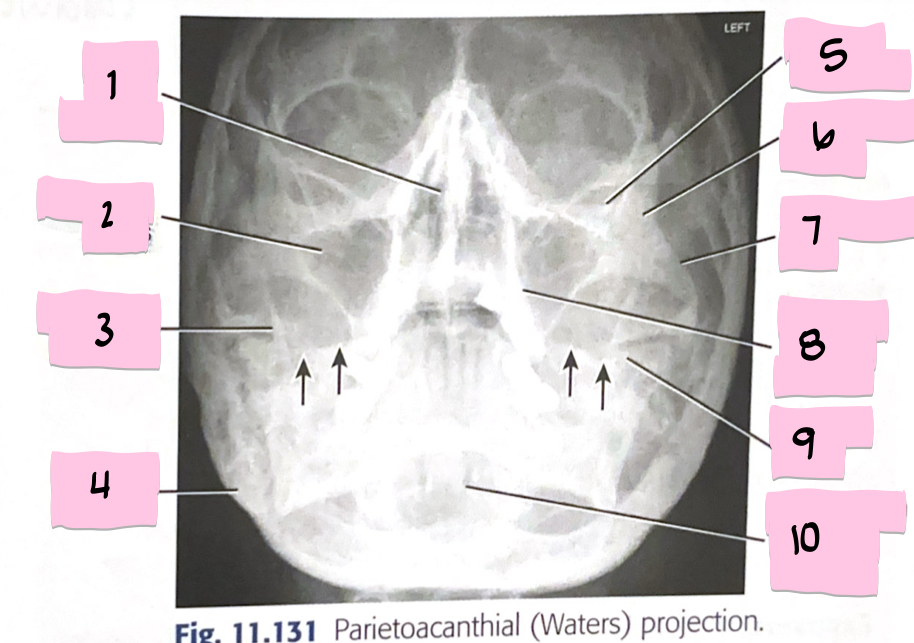

What is 1 pointing to?

Bony nasal septum

What is 2 pointing to?

Maxillary sinus

What is 3 pointing to?

Coronoid process

What is 4 pointing to?

Mastoid process

What is 5 pointing to?

Inferior orbital rim

What is 6 pointing to?

Zygomatic bone

What is 7 pointing to?

Zygomatic arch

What is 8 pointing to?

Maxillary alveolar process

What is 9 pointing to?

Petrous ridge

What is 10 pointing to?

Dens within foramen magnum